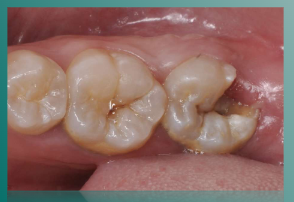

口内检查:胎面及远中面可见一大面积龋洞,内有大量腐质,呈黄褐色,龋坏范围较大,达牙本质深层,摇(-),叩(±),无明显松动,患侧由于长时间未使用,牙齿自洁功能差,周围牙龈红肿充血,摇易出血,牙石(+),口腔卫生较差。

CBCT显示:冠部远中大面积低密度影像,中部可见根管呈连续C形,舌侧牙体组织薄弱,根尖无明显低密度影像。

CBCT显示:冠部远中可见低密度影像近髓,远中龈壁位于骨上,近远中牙槽骨无明显吸收,报管影像清晰连续,近中报管下段明显弯曲,近远中报管在很尖融合,后方有一近中高位阻生智齿。

CBCT显示:冠部暗影面积较大,颊舌侧牙槽骨高度正常,无明显吸收,根尖无明显低密度影像。

诊断:47慢性牙髓炎急性发作